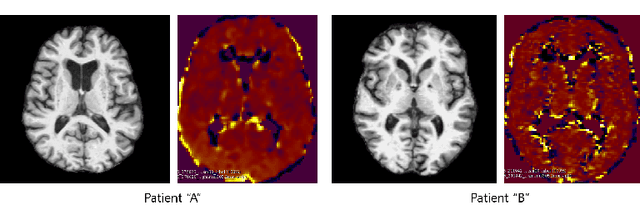

Abstract:Positron Emission Tomography (PET) is now regarded as the gold standard for the diagnosis of Alzheimer's Disease (AD). However, PET imaging can be prohibitive in terms of cost and planning, and is also among the imaging techniques with the highest dosage of radiation. Magnetic Resonance Imaging (MRI), in contrast, is more widely available and provides more flexibility when setting the desired image resolution. Unfortunately, the diagnosis of AD using MRI is difficult due to the very subtle physiological differences between healthy and AD subjects visible on MRI. As a result, many attempts have been made to synthesize PET images from MR images using generative adversarial networks (GANs) in the interest of enabling the diagnosis of AD from MR. Existing work on PET synthesis from MRI has largely focused on Conditional GANs, where MR images are used to generate PET images and subsequently used for AD diagnosis. There is no end-to-end training goal. This paper proposes an alternative approach to the aforementioned, where AD diagnosis is incorporated in the GAN training objective to achieve the best AD classification performance. Different GAN lossesare fine-tuned based on the discriminator performance, and the overall training is stabilized. The proposed network architecture and training regime show state-of-the-art performance for three- and four- class AD classification tasks.